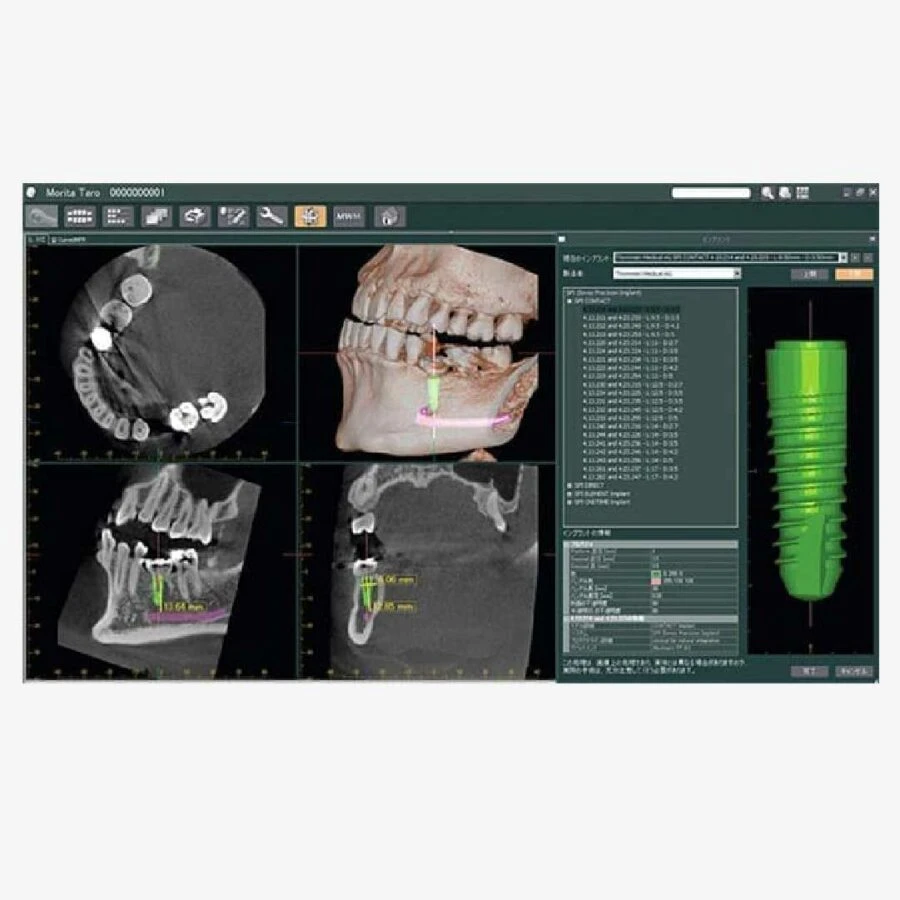

Xác nhận vị trí cấy ghép với hình ảnh mô phỏng 3D

Kết nối đến phần mềm mô phỏng cấy ghép

– Với 6 lựa chọn trường nhìn và chất lượng hình ảnh nổi tiếng thế giới của Morita, X550 phù hợp cho các ứng dụng đa dạng trong nha khoa bao gồm phương án cấy ghép.

– Khả năng chụp toàn bộ vòm miệng, giảm liều tia và rất rõ ràng là các đặc điểm lý tưởng cho việc lên kế hoạch cấy ghép và phẫu thuật miệng.